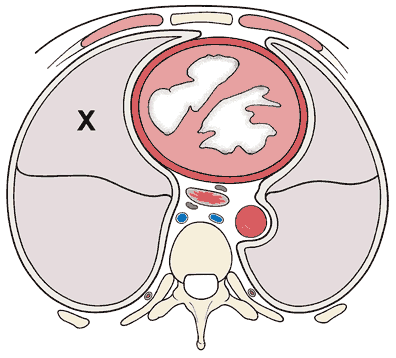

A 20-year-old man comes to the physician for a follow-up examination after blood pressure measurements were 175/105 mm Hg and 185/110 mm Hg 1 and 3 weeks ago, respectively. He is not obese, eats a healthy diet, and does not use illicit drugs. He has no family history of hypertension. His blood pressure now is 180/110 mm Hg. Physical examination shows no other abnormalities. Routine laboratory studies, including serum electrolyte concentrations, show no abnormalities. Antihypertensive treatment is started, but his blood pressure remains elevated at his next visit 3 weeks later, and his plasma renin activity is markedly increased in the left renal vein compared with the right renal vein. Renal angiography shows a pattern of “peaks and valleys” in the left renal artery. Which of the following is the most likely diagnosis?